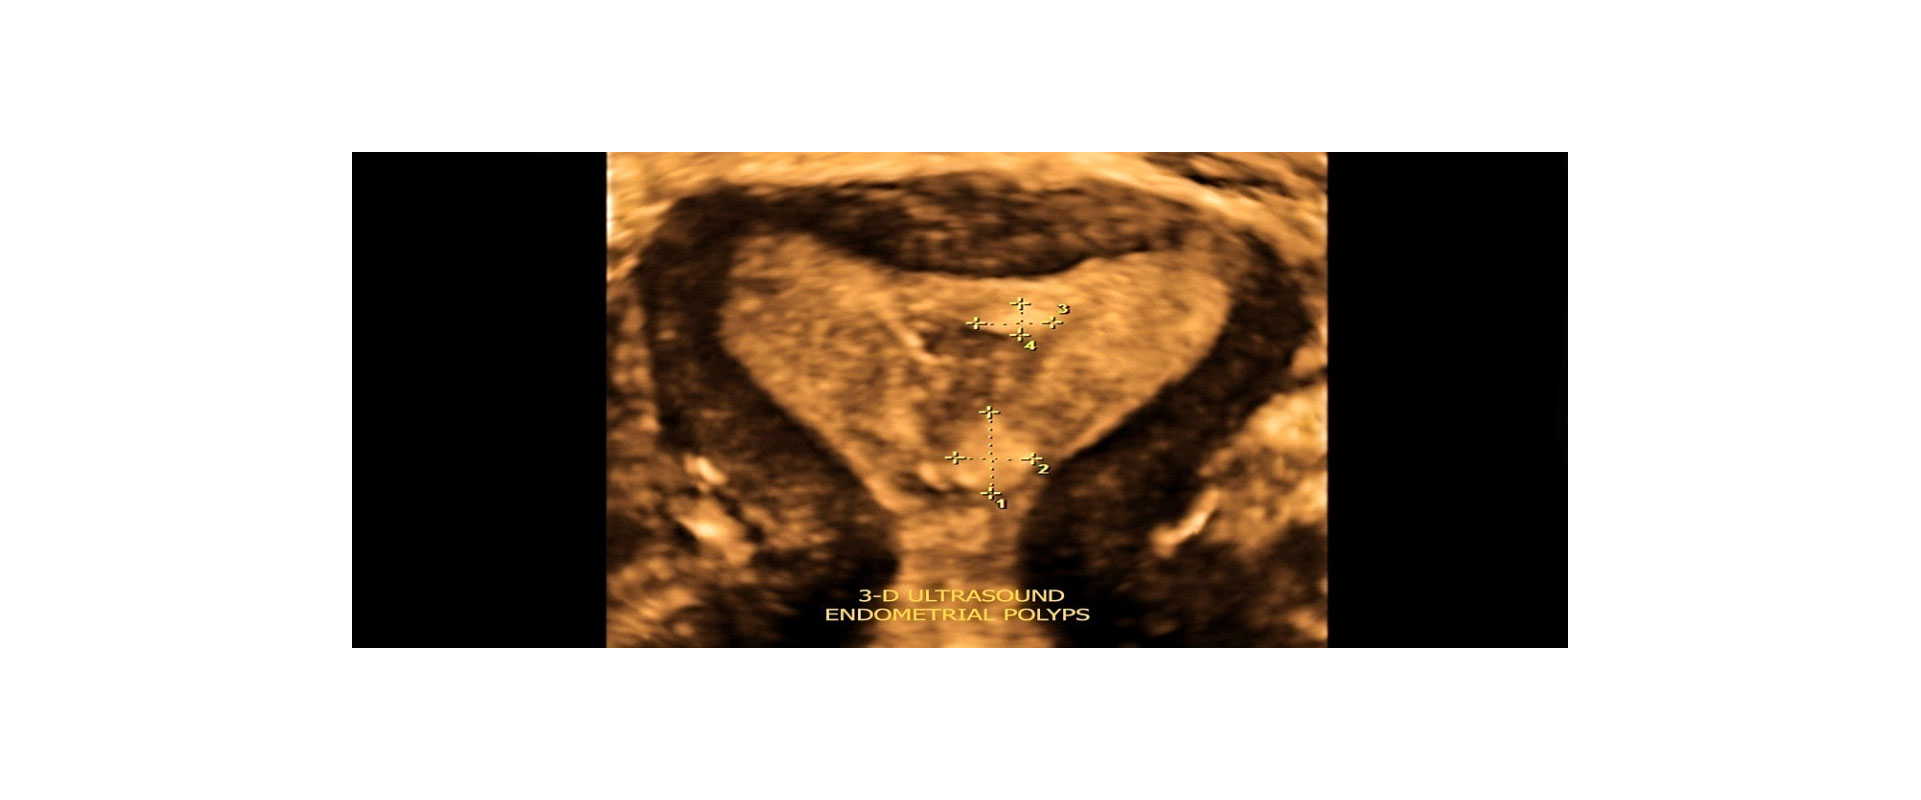

⦁ και τη φυσιολογική ανατομία της μήτρας και πιθανή παθολογία της

✓ Ακριβής Διάγνωση: Εξαιρετική ευκρίνεια εικόνων για τη διάγνωση γυναικολογικών προβλημάτων.

✓Εκτίμηση Ανατομίας: Βελτιωμένη ανάλυση της ανατομίας των γυναικείων αναπαραγωγικών οργάνων.